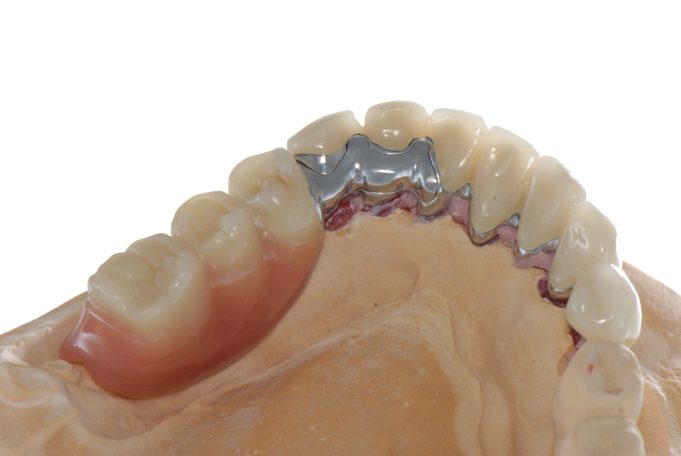

Implantsteg verankerte Brücke. Für den Patienten abnehmbar, aber der Tragekomfort von festen Zähnen.